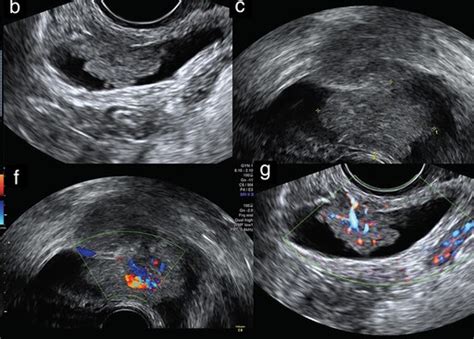

Diagnosticiranje splava običajno vključuje preverjanje odprtosti materničnega vratu in ultrazvočni pregled. Kvantitativna meritev serumskega β-hCG pomaga pri izključevanju zunajmaterničnih nosečnosti in ugotavljanju prisotnosti ostankov nosečnosti v maternici, kar kaže na nepopoln splav. Sum na zamujeni splav se pojavi, če se maternica ne povečuje ali je vrednost β-hCG nizka za gestacijsko starost. V primeru ponavljajočih se izgub nosečnosti je potrebno dodatno testiranje za ugotavljanje vzroka.